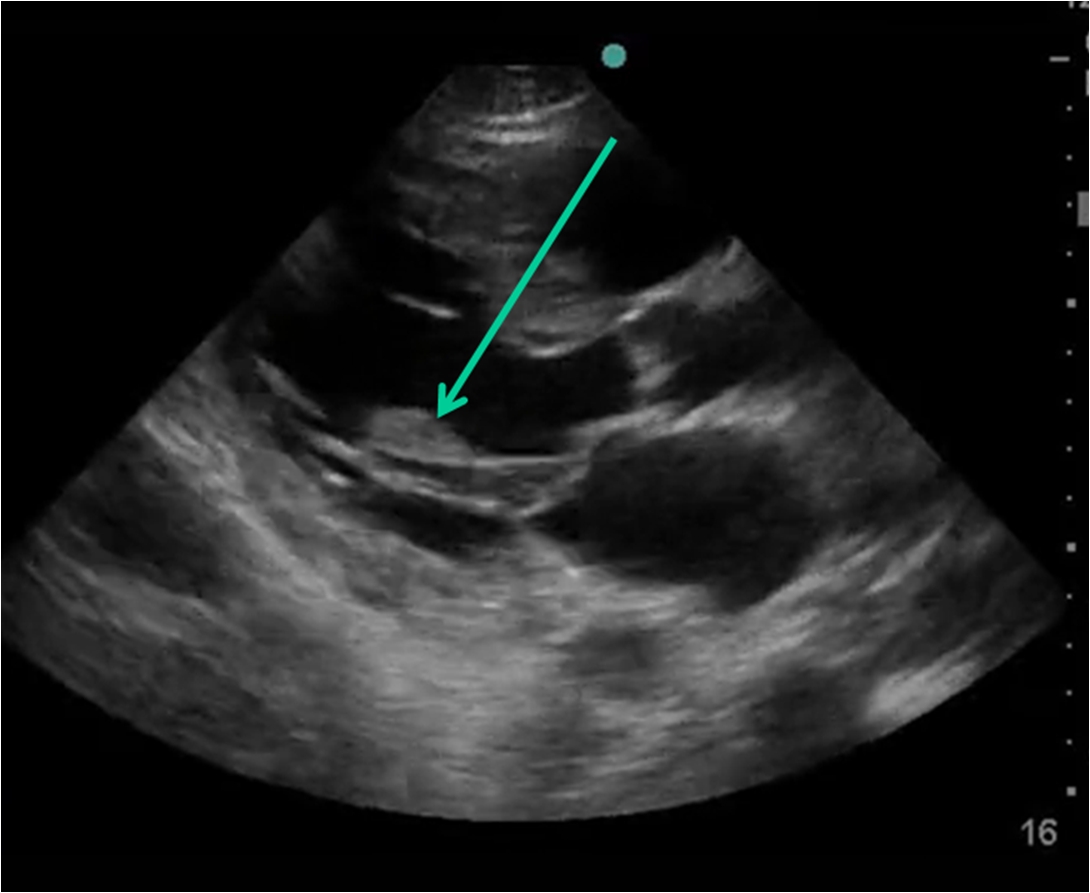

Ultrasound moderate Pericardial Effusion. Arrow shows echofree signal What Does An Arrow Mean In An Ultrasound in the center of the far field, you see another hyperechoic structure with acoustic shadowing behind it (green arrows), this time with an irregular border. An image showing what different colors mean on an. ultrasound reading entails giving meaning to the details in the ultrasound photo. So the first step to. the top of an ultrasound image. What Does An Arrow Mean In An Ultrasound.